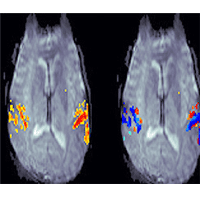

اسکن‌های جدید مغزی با استفاده از روش کاربردی MRI به محققان کمک می‌کند دریابند که چطور مغز موضوعات را در فضایی که فردی صداهای مختلف را می‌شنود، از یکدیگر مجزا می‌کند بدون اینکه لزوماً منابع چند گانه صداها را با چشم ببیند

اسکن‌های جدید مغزی با استفاده از روش کاربردی MRI به محققان کمک می‌کند دریابند که چطور مغز موضوعات را در فضایی که فردی صداهای مختلف را می‌شنود، از یکدیگر مجزا می‌کند بدون اینکه لزوماً منابع چند گانه صداها را با چشم ببیند.

گاهی اوقات صداها از موقعیت‌های مختلف نزدیک فرد و گاهی نیز چندین صدا از یک موقعیت منفرد به گوش می‌رسد. «صابری» و دستیارانش به دو نتیجه‌ی اصلی در این پژوهش رسیده‌اند؛ نخست این‌که یک ناحیه‌ی خاص در مغز به‌طور اختصاصی برای تشخیص حرکت صوتی به‌کار گرفته نمی‌شود در حالی‌که در عرض کورتکس بینایی مغز دارای مناطق خاص حسی - حرکتی است و دوم این‌که به‌نظر می‌رسد اطلاعات صوتی فضایی در یک منطقه‌ی عصبی موسوم به «گیجگاهی مسطح» پردازش می‌شوند به‌طوری که می‌تواند عمل مجزا کردن منابع صوتی چندگانه را تسهیل کند.